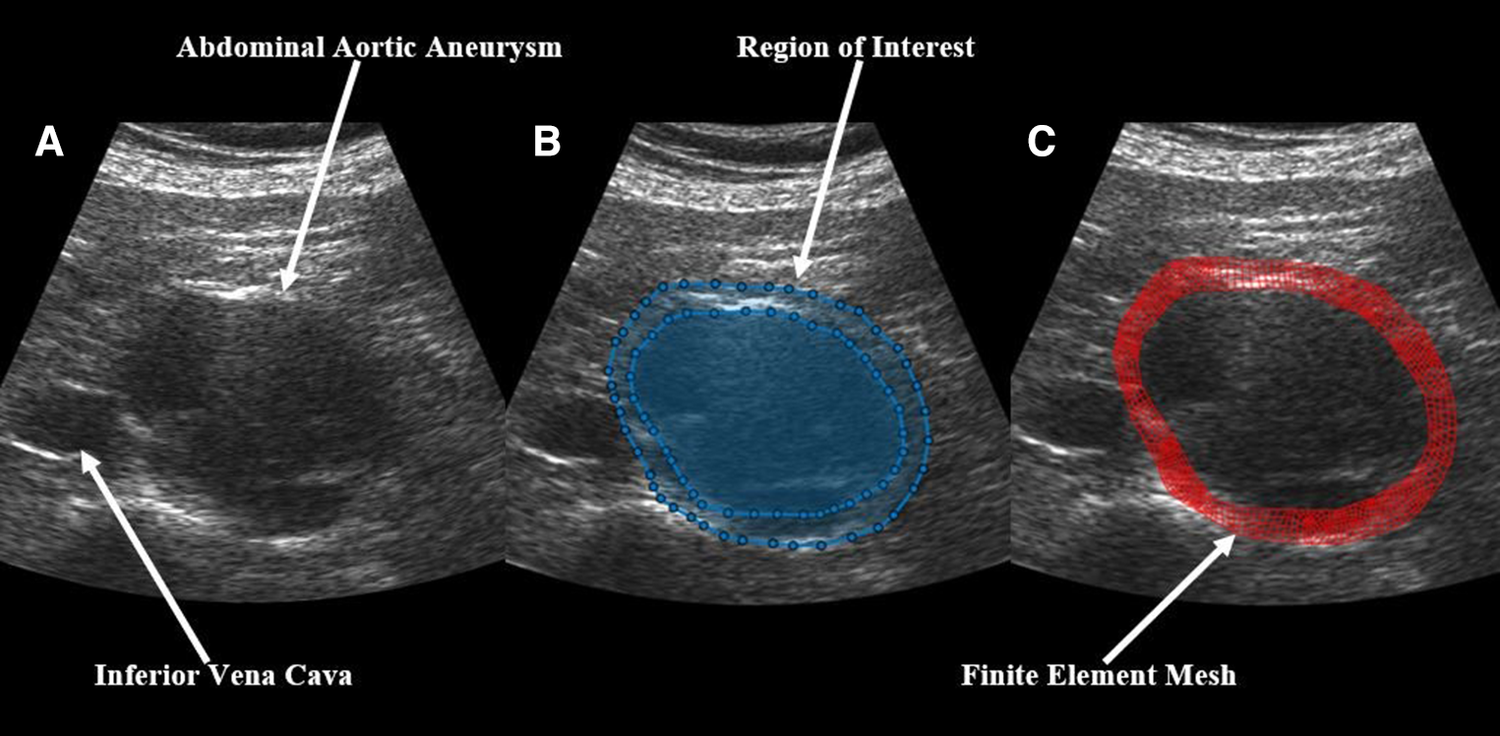

In brief, US RF data was converted to B-mode cine loops with the interpreter isolating the frames of one full cardiac cycle. The interpreter then marked the borders that would make up the region of interest for finite element mesh construction, with the first border representing the lumen of the vessel and the second border representing the outer wall of the vessel (Figure 1). Thrombus was included in the region selection as thrombus has been shown to impact strain and modulus calculations (13, 31). The displacement of each node within the constructed finite element mesh was then tracked from frame to frame to calculate the strain of each element within the mesh. The average strain of all elements within the mesh were then calculated to give the mean principal strain for a given frame. The accumulated spatial mean principal strains for each frame were then graphed, and the maximum mean principal strain () was determined. From here, parametric imaging was used to show principal regional strain within the entire aorta in the frame of (Figure 2). was then divided by pulse pressure taken at the time of the scan to produce /PP (27, 28). Additionally, a minimum regional cross-correlation (MRCC) value was calculated for all analyses, which is a value that assesses how well the image processing can maintain an adequate lock on the region of interest and is highly reliant on US image quality. A MRCC below zero was felt to represent an inadequate assessment of the patient's aorta and patients with a sub-zero value were excluded.

Figure 1

Demonstration of the construction of a finite element mesh over a patient's abdominal aortic aneurysm showing (A) a baseline B-mode ultrasound image, (B) the same ultrasound image with overlaid, user-identified regions of interest, and (C) the final finite element mesh construction over the patient's aorta.